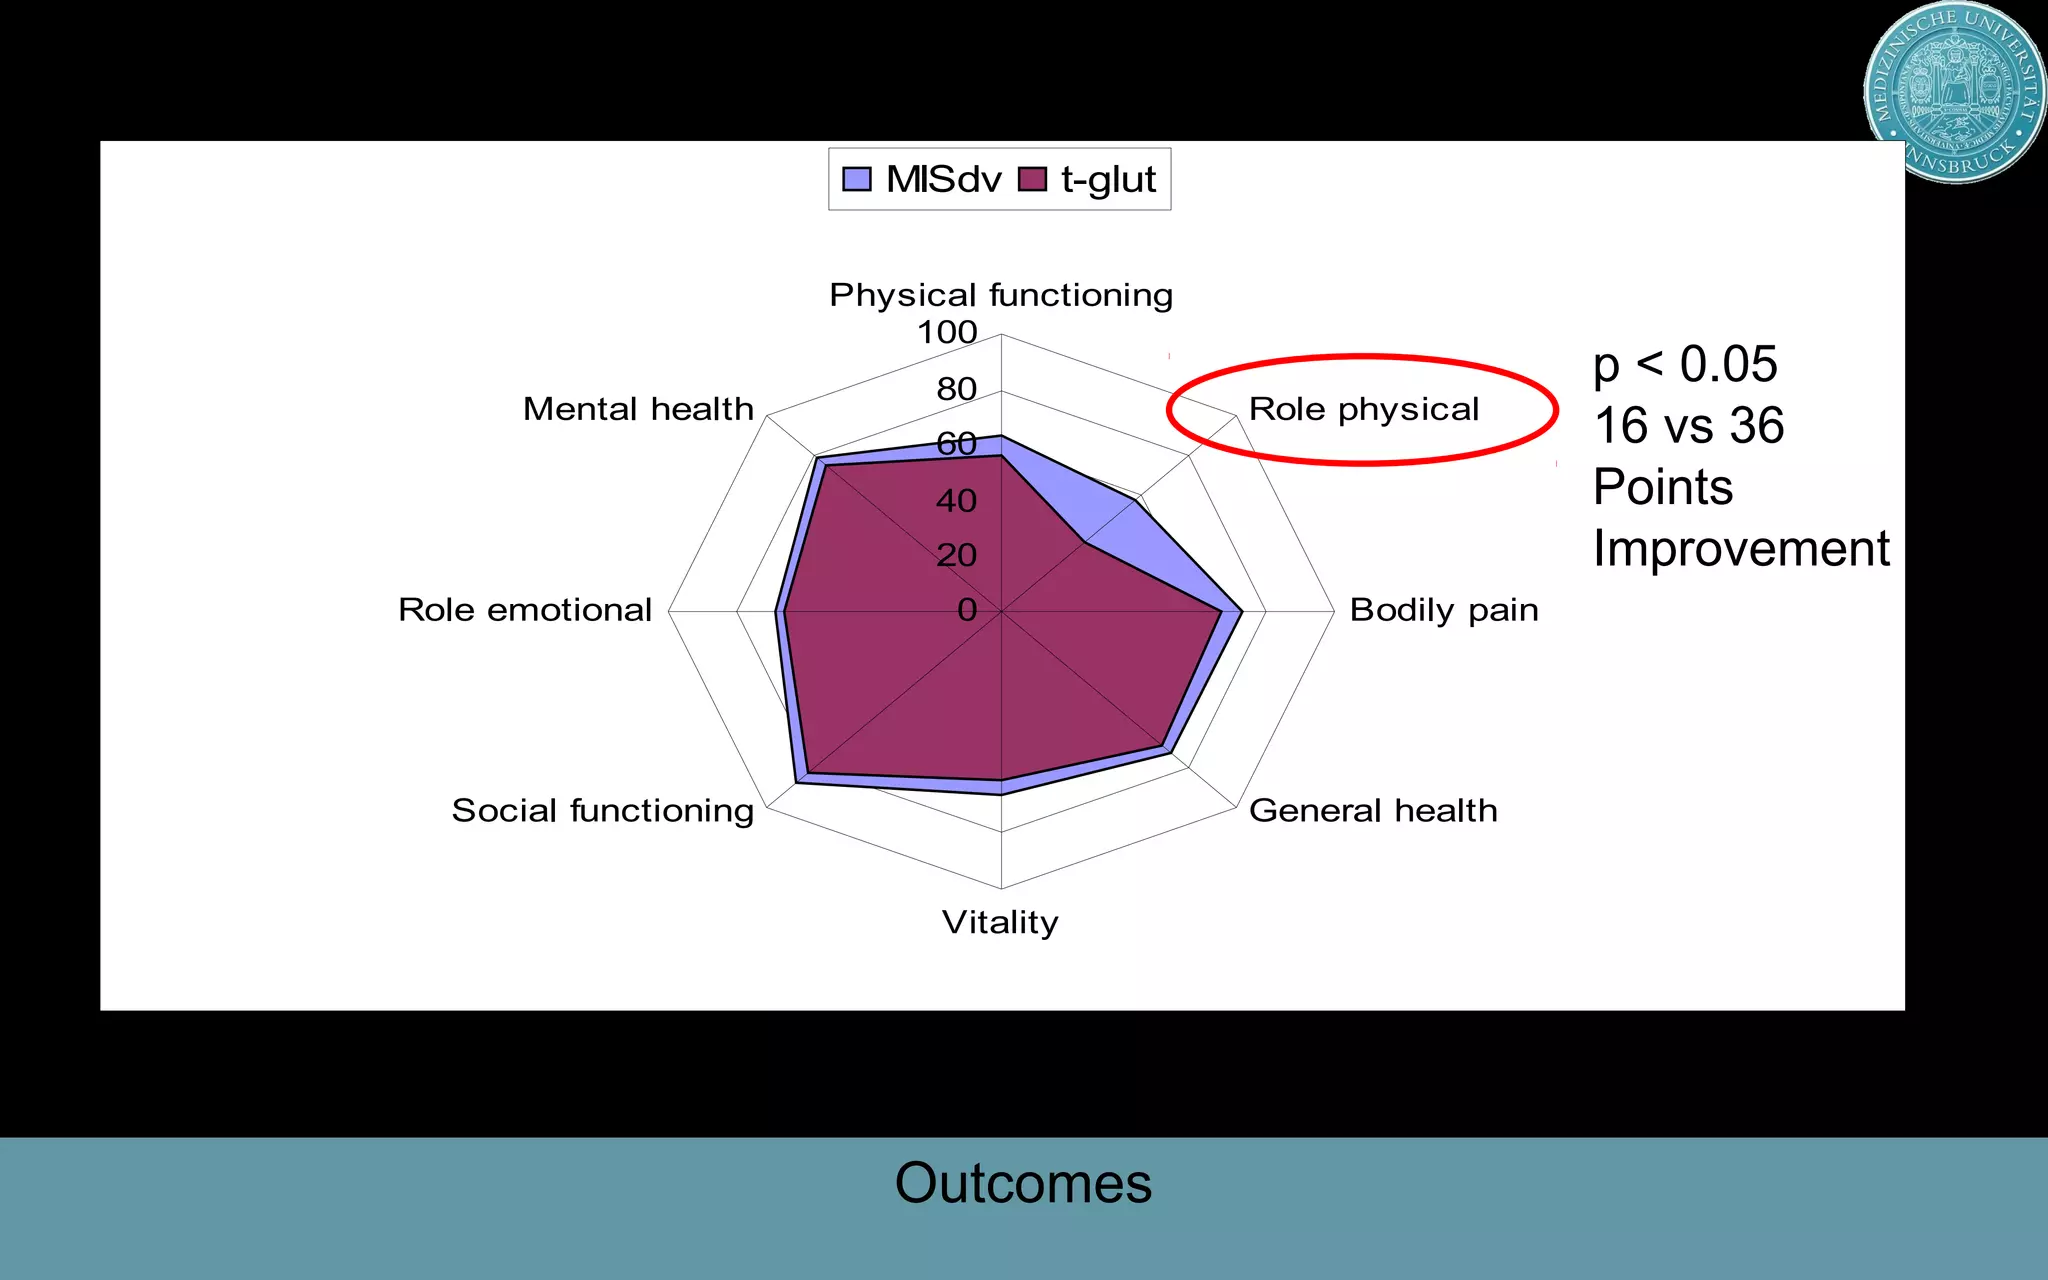

This document discusses the direct anterior approach for total hip arthroplasty. It lists advantages of the direct anterior approach such as increased stability, easier leg length equalization, lower costs by not requiring an operating table, reduced radiation exposure, faster rehabilitation, and lower risk of deep vein thrombosis. The document also discusses the historical background of the direct anterior approach, showing it has been performed since the 1880s. It presents images showing fatty degeneration of muscles and gluteal atrophy after total hip arthroplasty. Finally, it displays graphs comparing outcomes and improvements in quality of life domains between the direct anterior approach and minimally invasive approaches.